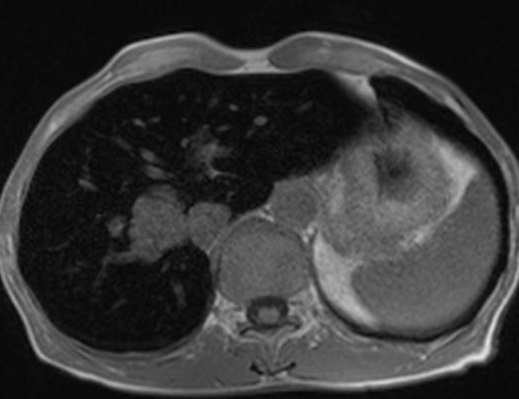

Image IRM de la cirrhose du foie : Cette

. Morphologie de la cirhose du foie sur IRM est

resemble que dans le CT et echographie . Aspect

radiologique IRM en T1 de cirrhose du foie est image

isosignal a bord et parenchyme irregulie

nodulaire et a hyposignal en T2 .

Aspect radiologique IRM en T1

d'une cirrhose du foie . Foie a petit taille

isointense a bord irregulier et splenomegalie

( coupe axiale ) . |

Cirrhose du foie en

coupe axiale IRM en T2 . Foie est

hyposignal |